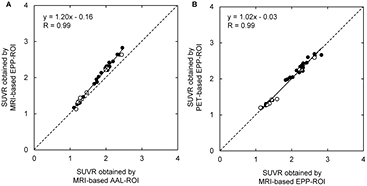

Standard image High-resolution imageFigure 7 shows the correlation between SUVRs obtained by MRI-based AAL-ROI method and MRI-based EPP-ROI method (A) and the correlation between SUVRs obtained by MRI-based EPP-ROI method and PET-based EPP-ROI method (B). Both showed a high correlation (R = 0.99, 0.99). Figure 8 shows individual SUVR values computed with the three methods in relation to clinical diagnosis. Most of the patients clinically diagnosed with AD or MCI showed higher SUVR. All normal control subjects showed lower SUVR. MRI-based EPP-ROI method provided higher SUVR than MRI-based AAL-ROI, while PET-based EPP-ROI and MRI-based EPP-ROI presented almost identical SUVR values.

Figure 7. Correlation between MRI-based AAL-ROI SUVR and MRI-based EPP-ROI SUVR (A) and corresponding correlation between MRI-based EPP-ROI SUVR and PET-based EPP-ROI SUVR (B). Black dots indicated subjects that were used to generate positive or negative templates.

We generated empirically PiB-prone ROI based on actual human PiB images. The results showed high correlation between SUVR obtained with MRI-based AAL-ROI and EPP-ROI (R = 0.99). The EPP-ROI provided higher SUVR than the AAL-ROI irrespective of positive or negative images, especially in positive images. This difference is considered to arise from exclusion of the voxels adjacent to the contour of the cortical area that are included in AAL-ROI, making EPP-ROI less sensitive to partial volume effect and normalization error. In a case with an error in the MRI-based gray matter segmentation as shown in figure 6, AAL-ROI extends beyond the cortical surface, leading to underestimation of SUVR. On the other hand, the EPP-ROI template is considered to provide more accurate and reproducible SUVR because it was derived from the cortical accumulation pattern of actual PiB images and does not contain voxels on the brain surface or gray–white border. Therefore the EPP-ROI has a potential to improve quantitative accuracy of amyloid quantification.